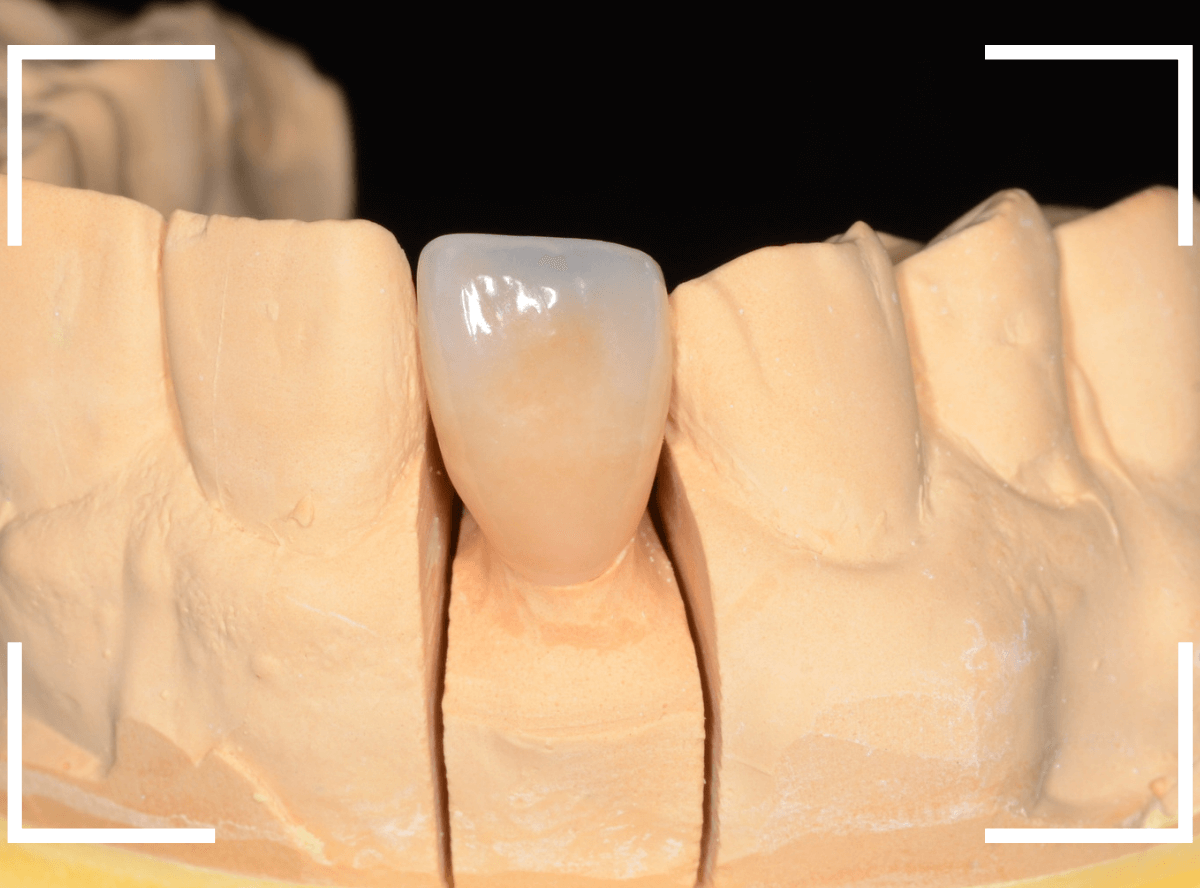

模型上で精密に制作します。

ジルコニア・セラミックは歯の内側や見えない部分にも一切金属を使用しないさし歯ですので、治療後の金属色で悩むこともありませんので、オススメです。

模型上で精密に製作します。

最終setしたところです。

前後の歯との色調も調和出来たかと思います。

患者さんにも喜んでいただけまして、ホッとしました。